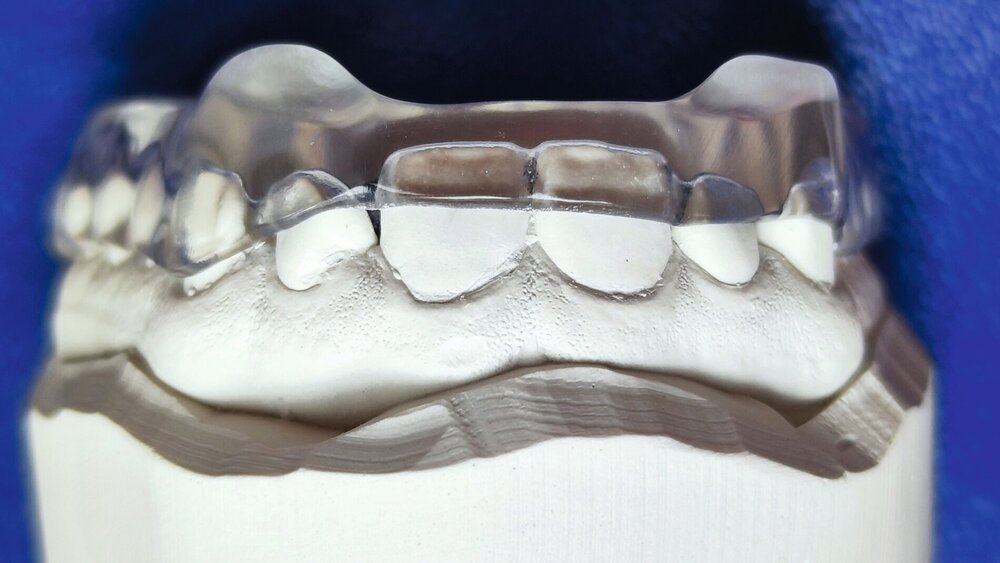

S: Schiene, vorzugsweise im Oberkiefer. Gegenüber einer Unterkiefer-Schiene ist eine Schiene im Oberkiefer weniger grazil und damit stabiler, zudem erlaubt sie mehr Raum für die Zunge. Im Fall der Michigan-Schiene, die klassischerweise – wenn immer möglich – im Oberkiefer hergestellt wird, wird die „Freiheit in der Zentrik“ palatinal gestaltet, was deutlich einfacher ist als im Fall einer Unterkiefer-Schiene, wo dies labial erfolgt. Hauptziele bei Bruxismus sind der Schutz der Zähne und der dentalen Restaurationen vor Abrieb sowie eine gleichmäßigere Verteilung der beim Bruxismus auftretenden Kräfte. Zudem führt die Schiene während des Tragens zu einer Neuorganisation der intramuskulären und intraartikulären Funktionsmuster, die eine Entlastung motorischer Einheiten und Gelenkstrukturen ermöglicht [Schindler et al., 2014]. Die Schiene der Wahl ist bei Personen ab 16 Jahren (Richtwert: die natürliche Feineinstellung der Okklusion ist zu diesem Zeitpunkt weitestgehend erfolgt) die Michigan-Schiene (Abbildungen 3 bis 5). Bei Personen unter 16 Jahren ist eine weiche Schiene im Oberkiefer zu empfehlen.

Terminologischer Hinweis: Bei den Kontakten der Zähne auf der Kunststoffoberfläche handelt es sich nicht um Okklusionskontakte.

© Türp, UZB; Labor: dental moeschli.ch, BaselNützliche Therapien